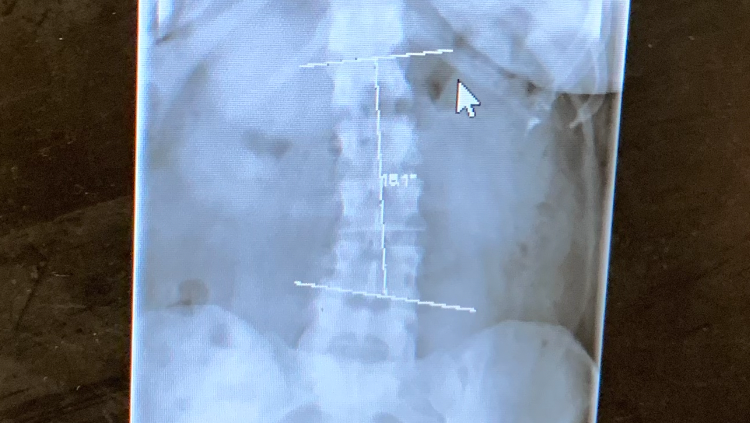

In 2006, I was diagnosed with a case of mononucleosis. While this is a fairly common virus- most never exhibiting any long term symptoms- I never seemed to get better. After years of seeing specialists, I was diagnosed with ME/CFS (Myalgic Encephalomyelitis/Chronic Fatigue Syndrome). This causes chronic, widespread pain & fatigue that does not improve with rest and many other symptoms that prevent me from functioning to my fullest on a day-to-day basis . I also have scoliosis that is incredibly painful at times and greatly impairs my ability to sleep comfortably.

This is an “invisible illness”, and most would never know how sick I am based off my appearance. Those close to me know that I have been struggling for years & how deeply this has affected me. My spine has an “S” curvature; I take medication 4x daily just to be able to move.

Scoliosis curvature (upper):

Scoliosis curvature (lower):